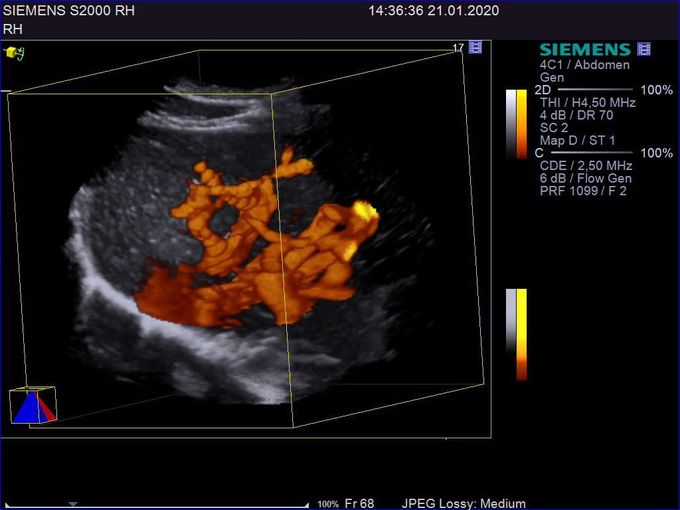

Кроме новой техники, можно заказать восстановленные медицинские системы: ультразвуковые сканеры, томографы, флюороскопы, ангиографы и хирургические установки С-дуга.